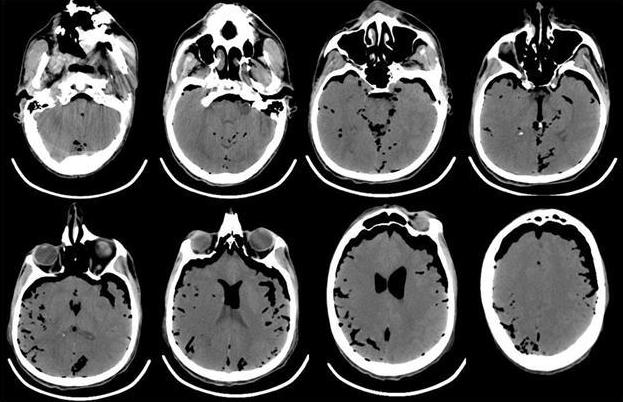

В связи с отсутствием признаков пробуждения в течение 2 ч и нарастанием неврологической симптоматики в виде появления анизокории (D>S) выполнена компьютерная томография головного мозга, выявившая массивную пневмоцефалию (рис. 4).

Рис. 4. КТ-головного мозга пациента, выполненная сразу после операции. Отмечается выраженная пневмоцефалия. В течение первых 12 ч после операции в структуре неврологического статуса у больного отмечалось нарастание общемозговой и очаговой неврологической симптоматики. Отсутствовала реакция на обращенную речь, болевое и струйное раздражение лица. При пассивном поднимании век взор неподвижный, двусторонний мидриаз без фотореакции. Роговичные, окулоцефалический и кашлевой рефлексы отсутствуют. Мышечная атония, арефлексия. Гемодинамика с тенденцией к артериальной гипотензии, несмотря на возрастающие дозы норадреналина максимально до 5 мкг/кг в минуту. Выполненная повторная КТ через 12 ч с момента поступления из операционной выявила диффузный отек головного мозга с отсутствием дифференцировки серого и белого вещества, пневмоцефалию (рис. 5).